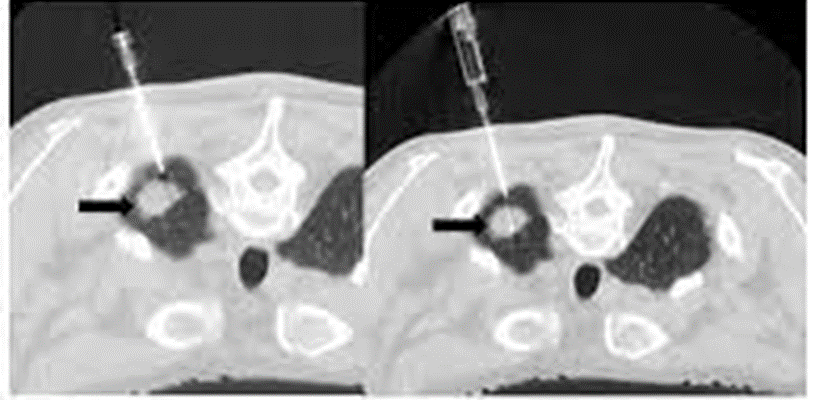

② CTガイド下生検

CTガイド下生検は、気管支鏡が届かない末梢病変や腫瘍に気管支の枝が入っていない病変では良い適応になります。(肺尖部や肺底部などは気管支鏡が届かない病変の代表です)

(日本IVR学会HPより)

CTガイド下生検は肺だけでなく、CTガイド下で骨や胸膜を生検する場合もあります。